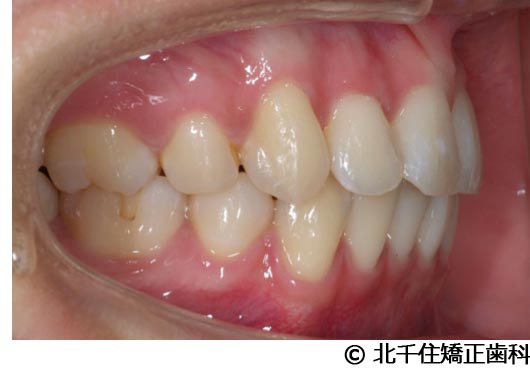

【症例5】上顎前突

- 治療前

- 治療後

- 治療名

- 上顎前突

- 費用

- 1,263,600円(税込)

- 期間

- 2年8ヵ月

- 治療回数

- 32回

- 通院頻度

- 1ヵ月ごと

- 年齢

- 13歳3ヵ月(初診時)

治療内容

-

患者様の症状

主訴:出っ歯

治療方法

骨格性の上顎前突、ヘッドギアを併用して上下顎第一小臼歯4本抜歯してワイヤー矯正。

治療結果

骨格性上顎前突に対し、ヘッドギアおよび抜歯を併用した矯正治療により歯列および咬合関係の調整を行った症例である。

治療後は保定装置を使用し、歯列および咬合の安定維持を目的として定期的な経過観察を行っている。

※治療結果は個人差があります。

治療を行う上での注意点(リスク・副作用)

歯磨き不良に伴うカリエスや歯周病、歯根吸収など。